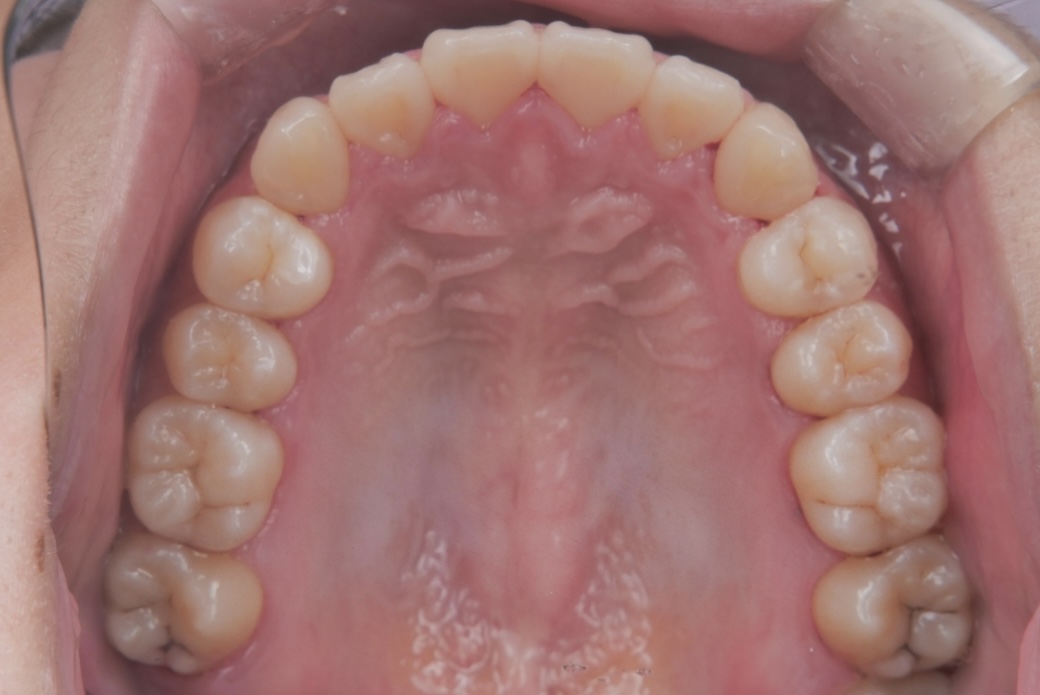

BEFORE

大学生女性 ガタガタが気になる

大学生の女性の患者さまで、ガタガタした歯並びをできるだけ痛みの少ない方法で整えたいとご相談に来院されました。